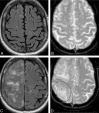

Background and purpose: AD is one of the few leading causes of death without a disease-modifying drug; however, hopeful agents are in various phases of development. MR imaging abnormalities, collectively referred to as amyloid-related imaging abnormalities, have been reported for several agents that target cerebral Aβ burden. ARIA includes ARIA-E, parenchymal or sulcal hyperintensities on FLAIR indicative of parenchymal edema or sulcal effusions, and ARIA-H, hypointense regions on gradient recalled-echo/T2* indicative of hemosiderin deposition. This report describes imaging characteristics of ARIA-E and ARIA-H identified during studies of bapineuzumab, a humanized monoclonal antibody against Aβ.

Results: Thirty-six patients were identified with incident ARIA-E (17.1%, 36/210) and 26 with incident ARIA-H (12.4%, 26/210); of those with incident ARIA-H, 24 had incident microhemorrhages and 2 had incident large superficial hemosiderin deposits.

Conclusions: In 49% of cases of ARIA-E, there was the associated appearance of ARIA-H. In treated patients without ARIA-E, the risk for incident blood products was 4%. This association between ARIA-E and ARIA-H may suggest a common pathophysiologic mechanism. Familiarity with ARIA should permit radiologists and clinicians to recognize and communicate ARIA findings more reliably for optimal patient management.